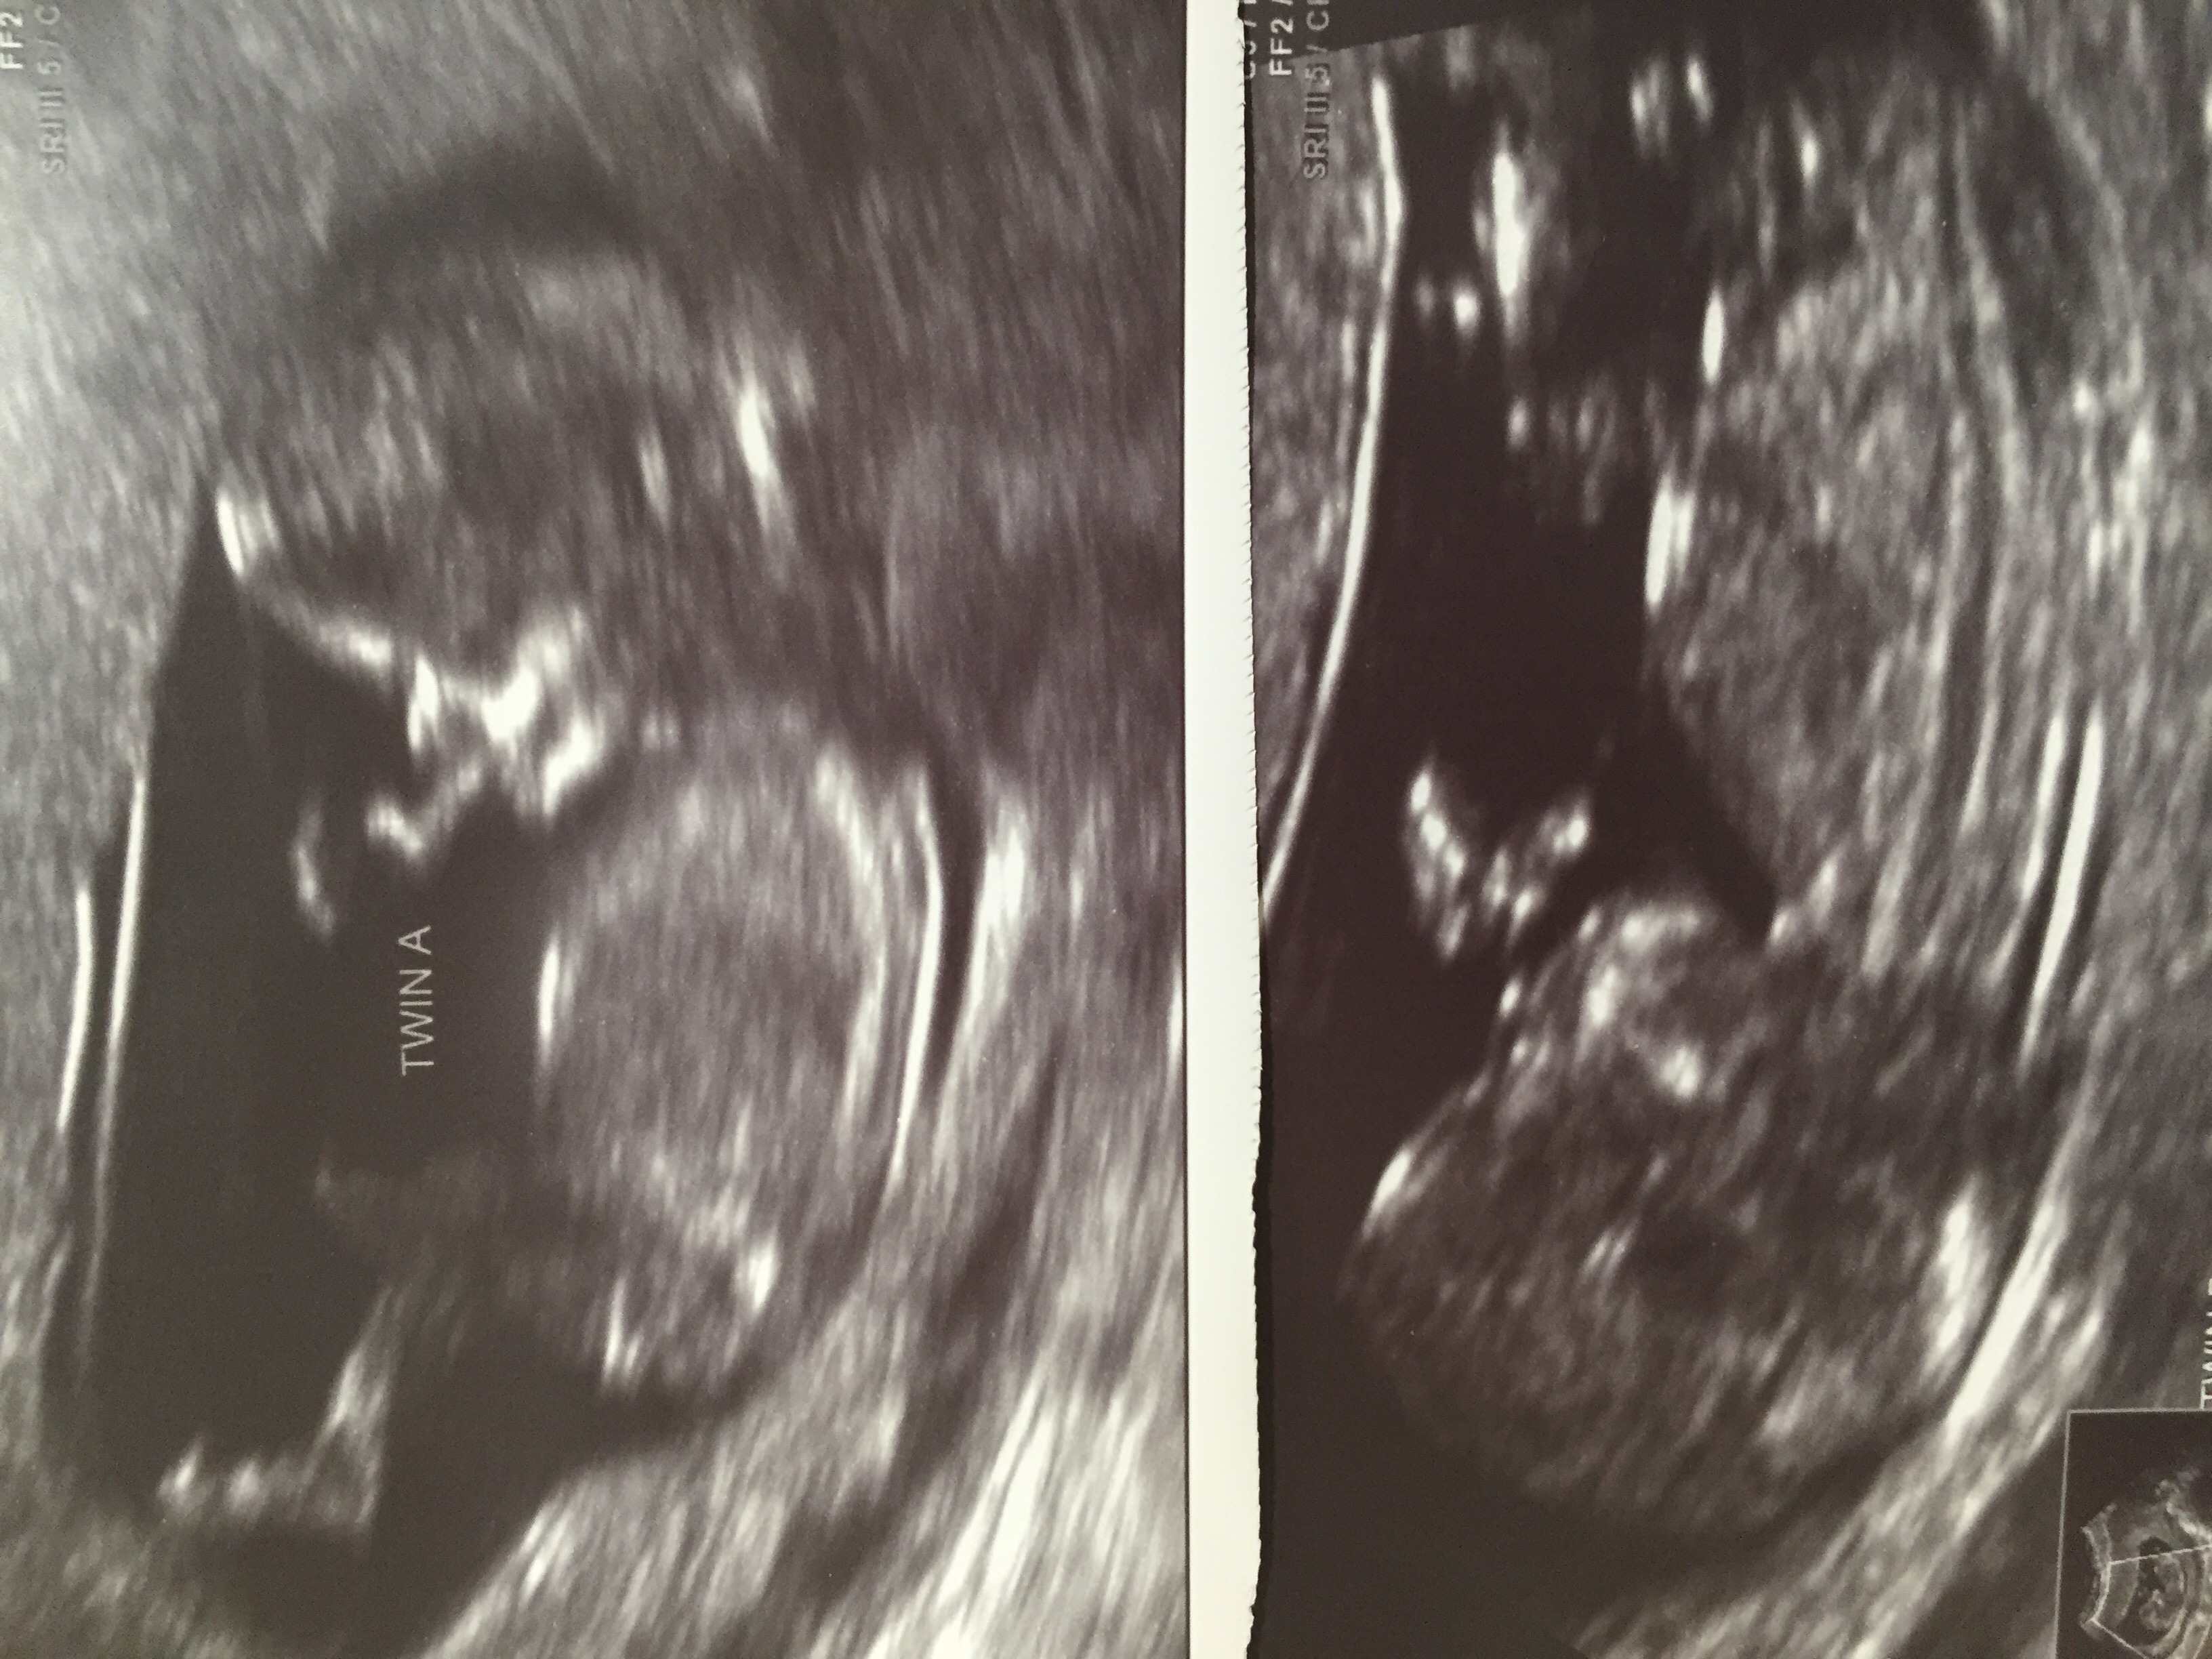

Hi All!! I would love your opinions on our 12w2d twin u/s!!!! We were told conflicting guesses from techs at this scan and 13w follow up! TIA!!! Attachment 24998

A Looks like a solid girl. B maybe as well but it's borderline

A looks like a girl, b is hard to tell.

Twin A: 100% sure :princess: Twin B, looks girl but kind of hard to tell. I think it's a girl, but we shall see! ;)

It looks girl/girl to me. Even their heads have the same shape